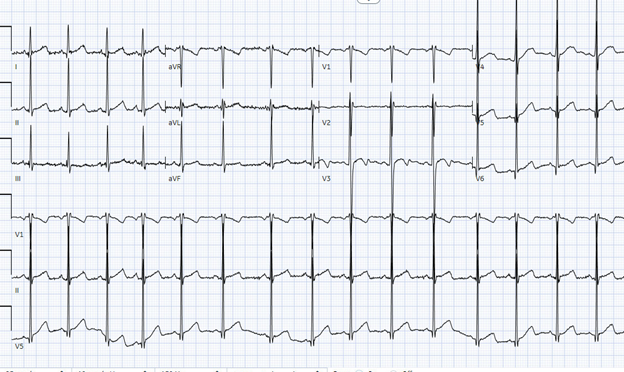

Initial workup showed an electrocardiogram (Figure 1) with left ventricular hypertrophy (LVH) and Q waves in the lateral leads.

Figure 1